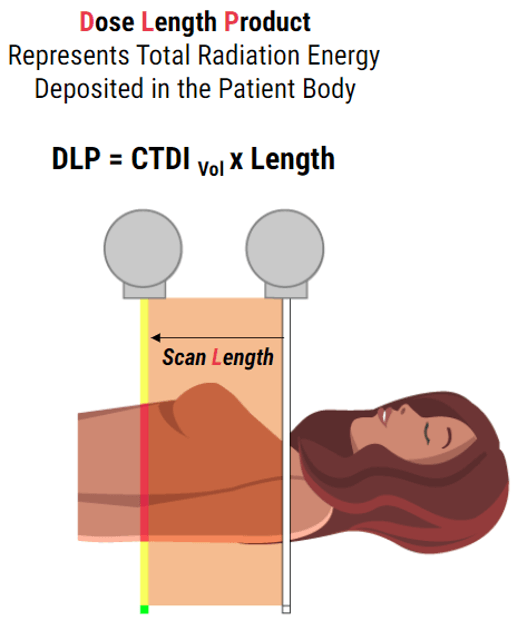

Dose Length Product

Currently, the quantity that is being used as an indicator of patient dose from CT examinations is the dose–length product (DLP). The effective dose can be calculated from the DLP using conversion coefficients that have been proposed for specific routine examinations or by using special software. This gives us the measurement of the total amount of exposure for a series of scans as opposed to one slice. This is dependent on and directly proportional to the scan length. It is the product of the CTDIvol and the scan length.

Documentation: Concerns over patient radiation doses are valid. Because CT scans can deposit more radiation dose per examination than other imaging modalities and its use has dramatically increased over the past 10 years, it is important to document doses. Monitoring patient radiation dose must also be performed during Ct guided interventions. In CT-guided procedures, the initial localizing scan contributes the most to effective dose because it is distributed over a large area.

The ability to monitor CT dose metrics is limited by the individual hospital infrastructure and finance, their staff and by the scanner itself. Multiple approaches to gathering data may be required. Estimated radiation dose should be recorded in the medical record, preferably the formal procedure report, for every procedure. Existing Society of Interventional Radiology (SIR) Safety and Health Committee (SIR) guidelines for recording patient radiation dose should be followed.